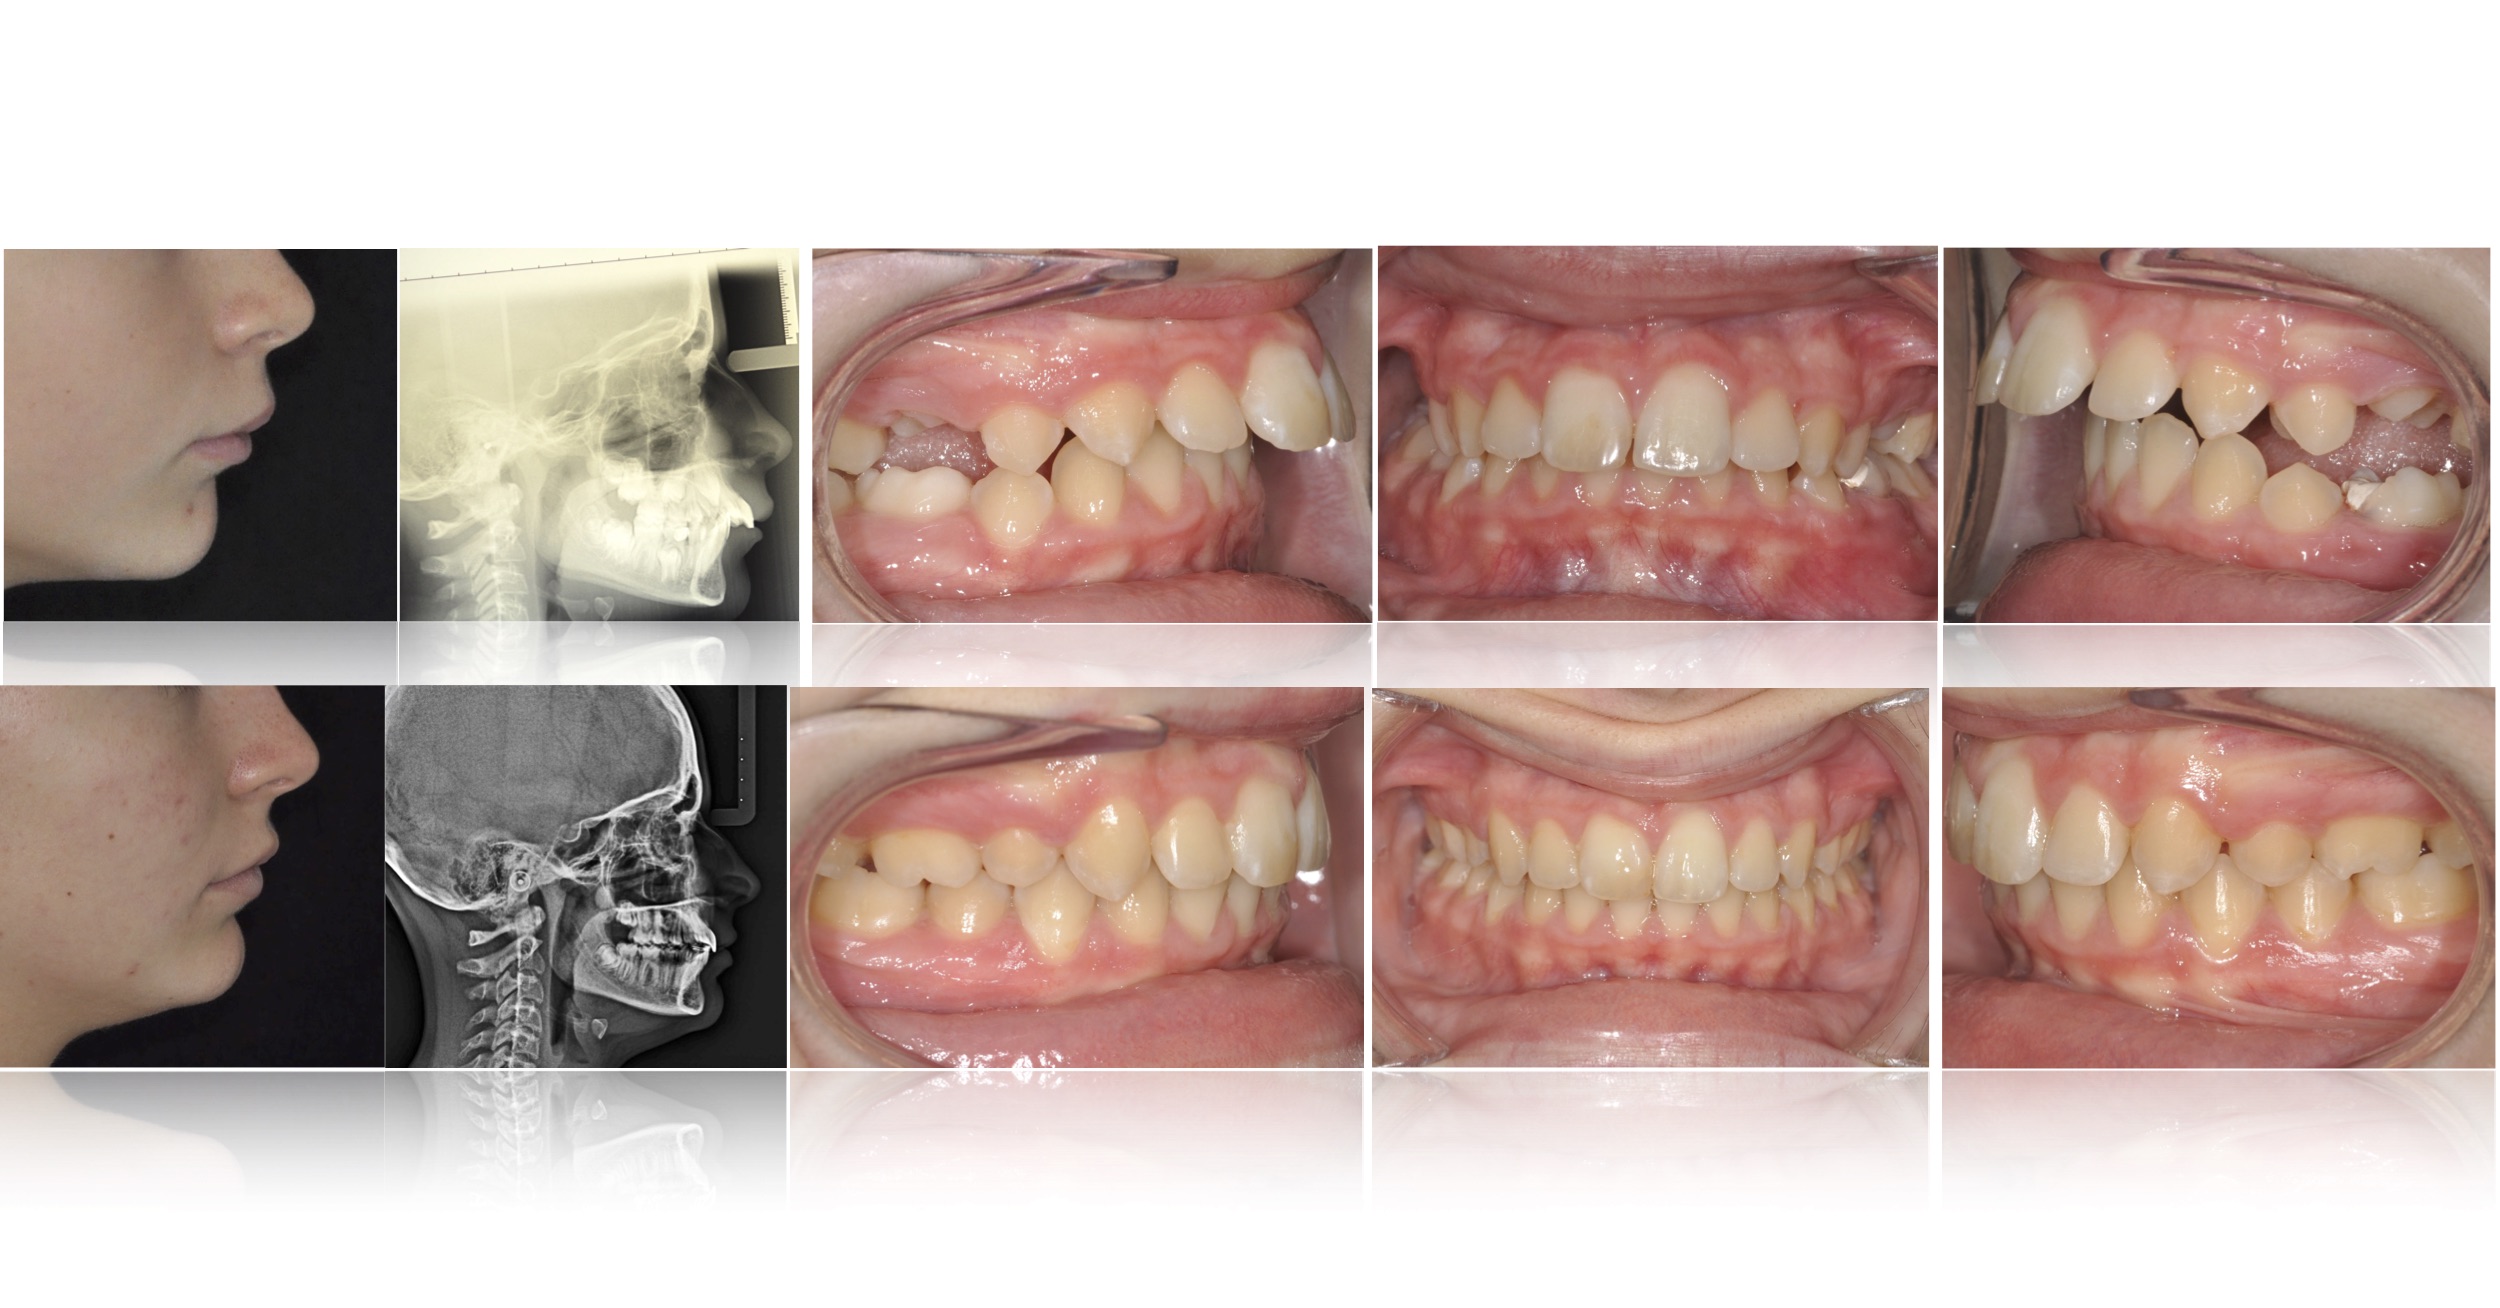

Hanno solitamente pelle color verde spento, grossolani capelli scuri, piccoli occhi rossi e denti sporgenti, simili a zanne Gli orchi considerano le cicatrici un segno di distinzione e spesso le utilizzano come una forma d'arte Nomi Maschili Arkus, Carrug, Felzak, Murdut, Prabur Femminili Durra, Grillgiss, Ilyat, Krugga, Leffit, Olbin. Denti sporgenti esempio di correzione 3 Febbraio 19 7 Dicembre 17 di Dr Tito Mattia Bordino I denti sporgenti ( video ) sono un problema estetico che i pazienti non accettano. Il termine denti sporgenti viene utilizzato generalmente per indicare una condizione in cui i denti anteriori, solitamente molto grandi, sporgono sul labbro andando a coprire anche il labbro inferiore.

Denti Sporgenti Esempio Di Correzione Ortodonzia Torino